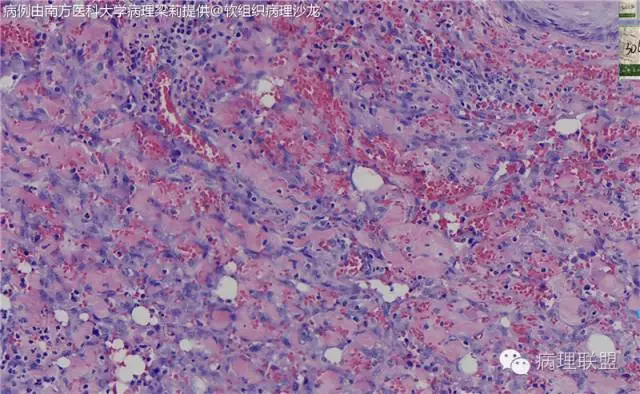

血管裂隙样,弯曲排列,似迷宫样,良性应该打不住,需往中间型考虑,请大咖们指点,软组织的重点应该放在良恶性的鉴别吧。

这例我们发的是卡波西样血管内皮细胞瘤,考虑如下:(1)新生儿,肢体肿物;(2)位置深,侵及皮下脂肪;(3)大多是裂隙状血管,也有少量吻合的血管网,细胞有异形,可见坏死

Kaposi型血管内皮瘤常有隐约小叶结构,梭形细胞束间有毛细血管,细胞核异型性和分裂活性一般不明显,常见梭形细胞束和圆形"肾小球样"实性细胞巢混合存在。

有些区域类似Kaposi肉瘤,如下图